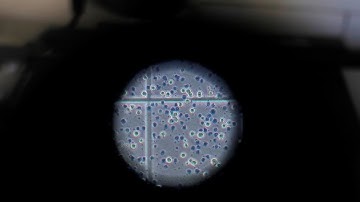

COVID-19: Testing live Omicron samples in a Glasgow lab